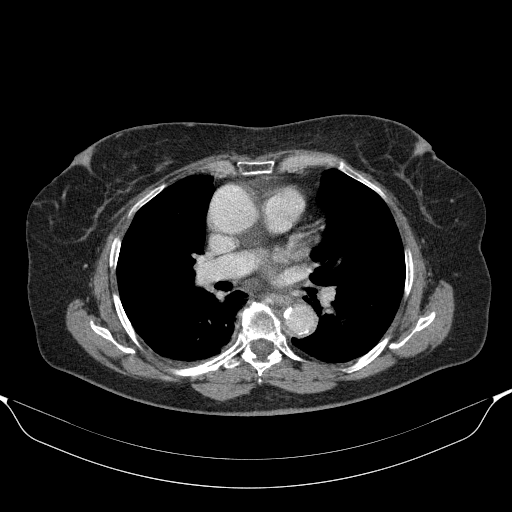

Image Grid

4Γ—3 grid: Rows show different image types (Original NATIVE, Reconstructed NATIVE, Original VENOUS, Generated VENOUS), Columns show windowing techniques (No Window, Lung Window, Mediastinum Window)

Original VENOUS CT scan

Full window (WL 1023.5, WW 4095 β†’ Low βˆ’1024, High +3071)

Generated VENOUS CT scan (A→B translation)